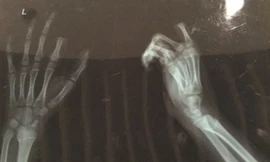

Người đàn ông đứng giữa đường dường như đang đợi sang bên kia. Ôtô thứ nhất vụt qua và chèn vào gót chân phải khiến người này đau đớn ngã xuống đất. Ôtô thứ hai lao tới và chèn qua người nạn nhân. Ôtô thứ 3 dừng kịp khi được báo hiệu nhưng xe phía sau không kịp phanh, húc tới và đẩy ôtô thứ 3 chèn lên người đàn ông đang nằm trên đường. Theo truyền thông thành phố Côn Sơn, tỉnh Tô Châu, Trung Quốc, nạn nhân bị rạn xương chân và gãy 6 chiếc xương khác nhưng bình phục khá tốt.